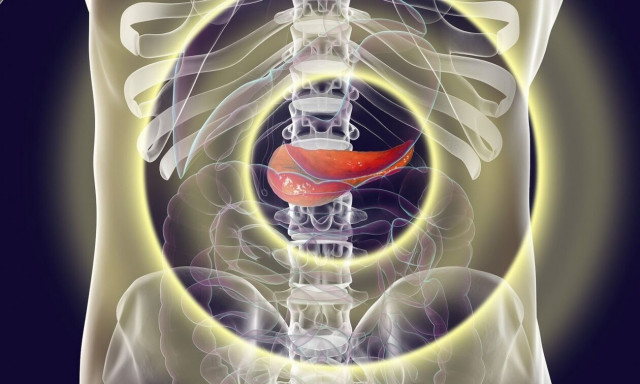

Καρκίνος στο πάγκρεας: Οι παράγοντες που οδηγούν στη μετάσταση

Ο καρκίνος του παγκρέατος αποτελεί την τρίτη αιτία θανάτου από καρκίνο στις Ηνωμένες Πολιτείες και μόνο το 12% των ασθενών επιβιώνει πέντε χρόνια μετά τη διάγνωση.

Ο σοβαρός καρκίνος του παγκρέατος σχετίζεται με μετάσταση, δηλαδή εξάπλωση δευτερογενών όγκων που συνήθως προκαλεί το θάνατο, λίγα ωστόσο είναι γνωστά για τους μοριακούς μηχανισμούς που οδηγούν στη μετάσταση.